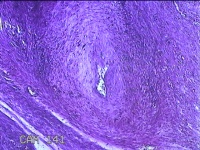

子宫肌瘤

性别

女

年龄

38岁

临床诊断

一般病史

发现子宫肌瘤复发7年余。

标本名称

大体所见

灰白粉红色结节样肿物8.5x5.5x4cm一个,表面糜烂,切面灰白色,编织状,质中。

富于细胞性平滑肌瘤

考虑富细胞平滑肌瘤。

组织处理和染色都不太理想。